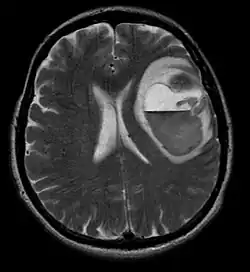

MRI głowy u 59-letniej chorej z afazją, hemiplegią i splątaniem. Przerzut czerniaka z krwiakiem

Badania radiologiczne znajdują zastosowanie przede wszystkim w ocenie zaawansowania klinicznego i wykazują niewielką przydatność w pierwotnej diagnostyce czerniaka.

Rezonans magnetyczny (MRI)

Rezonans magnetyczny jest bardziej czułą metodą diagnostyczną niż tomografia komputerowa w wykrywaniu przerzutów w mózgu, rdzeniu kręgowym i oponach mózgowo-rdzeniowych. Jest to najlepsza metoda stwierdzająca patologiczną masę w szpiku kostnym. Rezonans magnetyczny pozwala na różnicowanie łagodnych nowotworów wątroby, w tym z naczyniakami, od nowotworu przerzutowego[136].